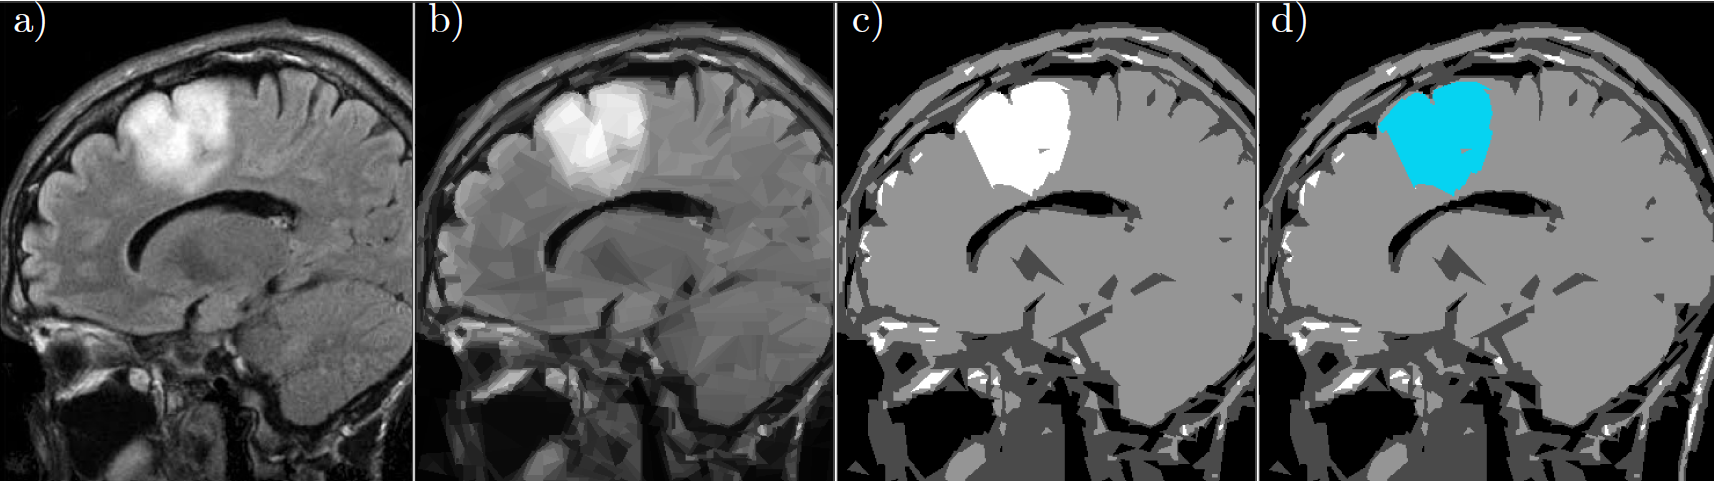

In a split-and-merge segmentation, a preliminary splitting method of the image is combined with a merging scheme for the calculated subregions in order to obtain a final segmentation of the image. The adaptive wedgelet decomposition presented above, combined with a classical merging strategy for subregions, yields in a simple way an efficient and robust segmentation of relevant subdomains. This wedgelet-based split-and-merge scheme can be used in the segmentation of biomedical images obtained by modalities as, for instance, Magnetic Resonance Imaging. As a test data set, we consider an MRI scan containing a glioma (in Fig. 6 a)) taken from a dataset on Kaggle. The aim of this experiment is to see whether the wedgelet-based split-and-merge scheme can segment the glioma from the rest of the image. For this, we conduct a wedgelet decomposition (Fig. 6 b), PSNR 27.68) to split the image in 2500 subregions. After the application of the merging algorithm, we obtain a segmentation of the image in 4 grayscales (Fig. 6 c)). The segment describing the region with the glioma is colored in blue (Fig. 6 d)).

Fig. 6: Wedgelet split-and-merge segmentation for biomedical images: a) Original MRI image with glioma b) Wedgelet split into $2500$ regions c) Segmentation obtained by merging the wegdgelet regions d) Blue colored segmented glioma